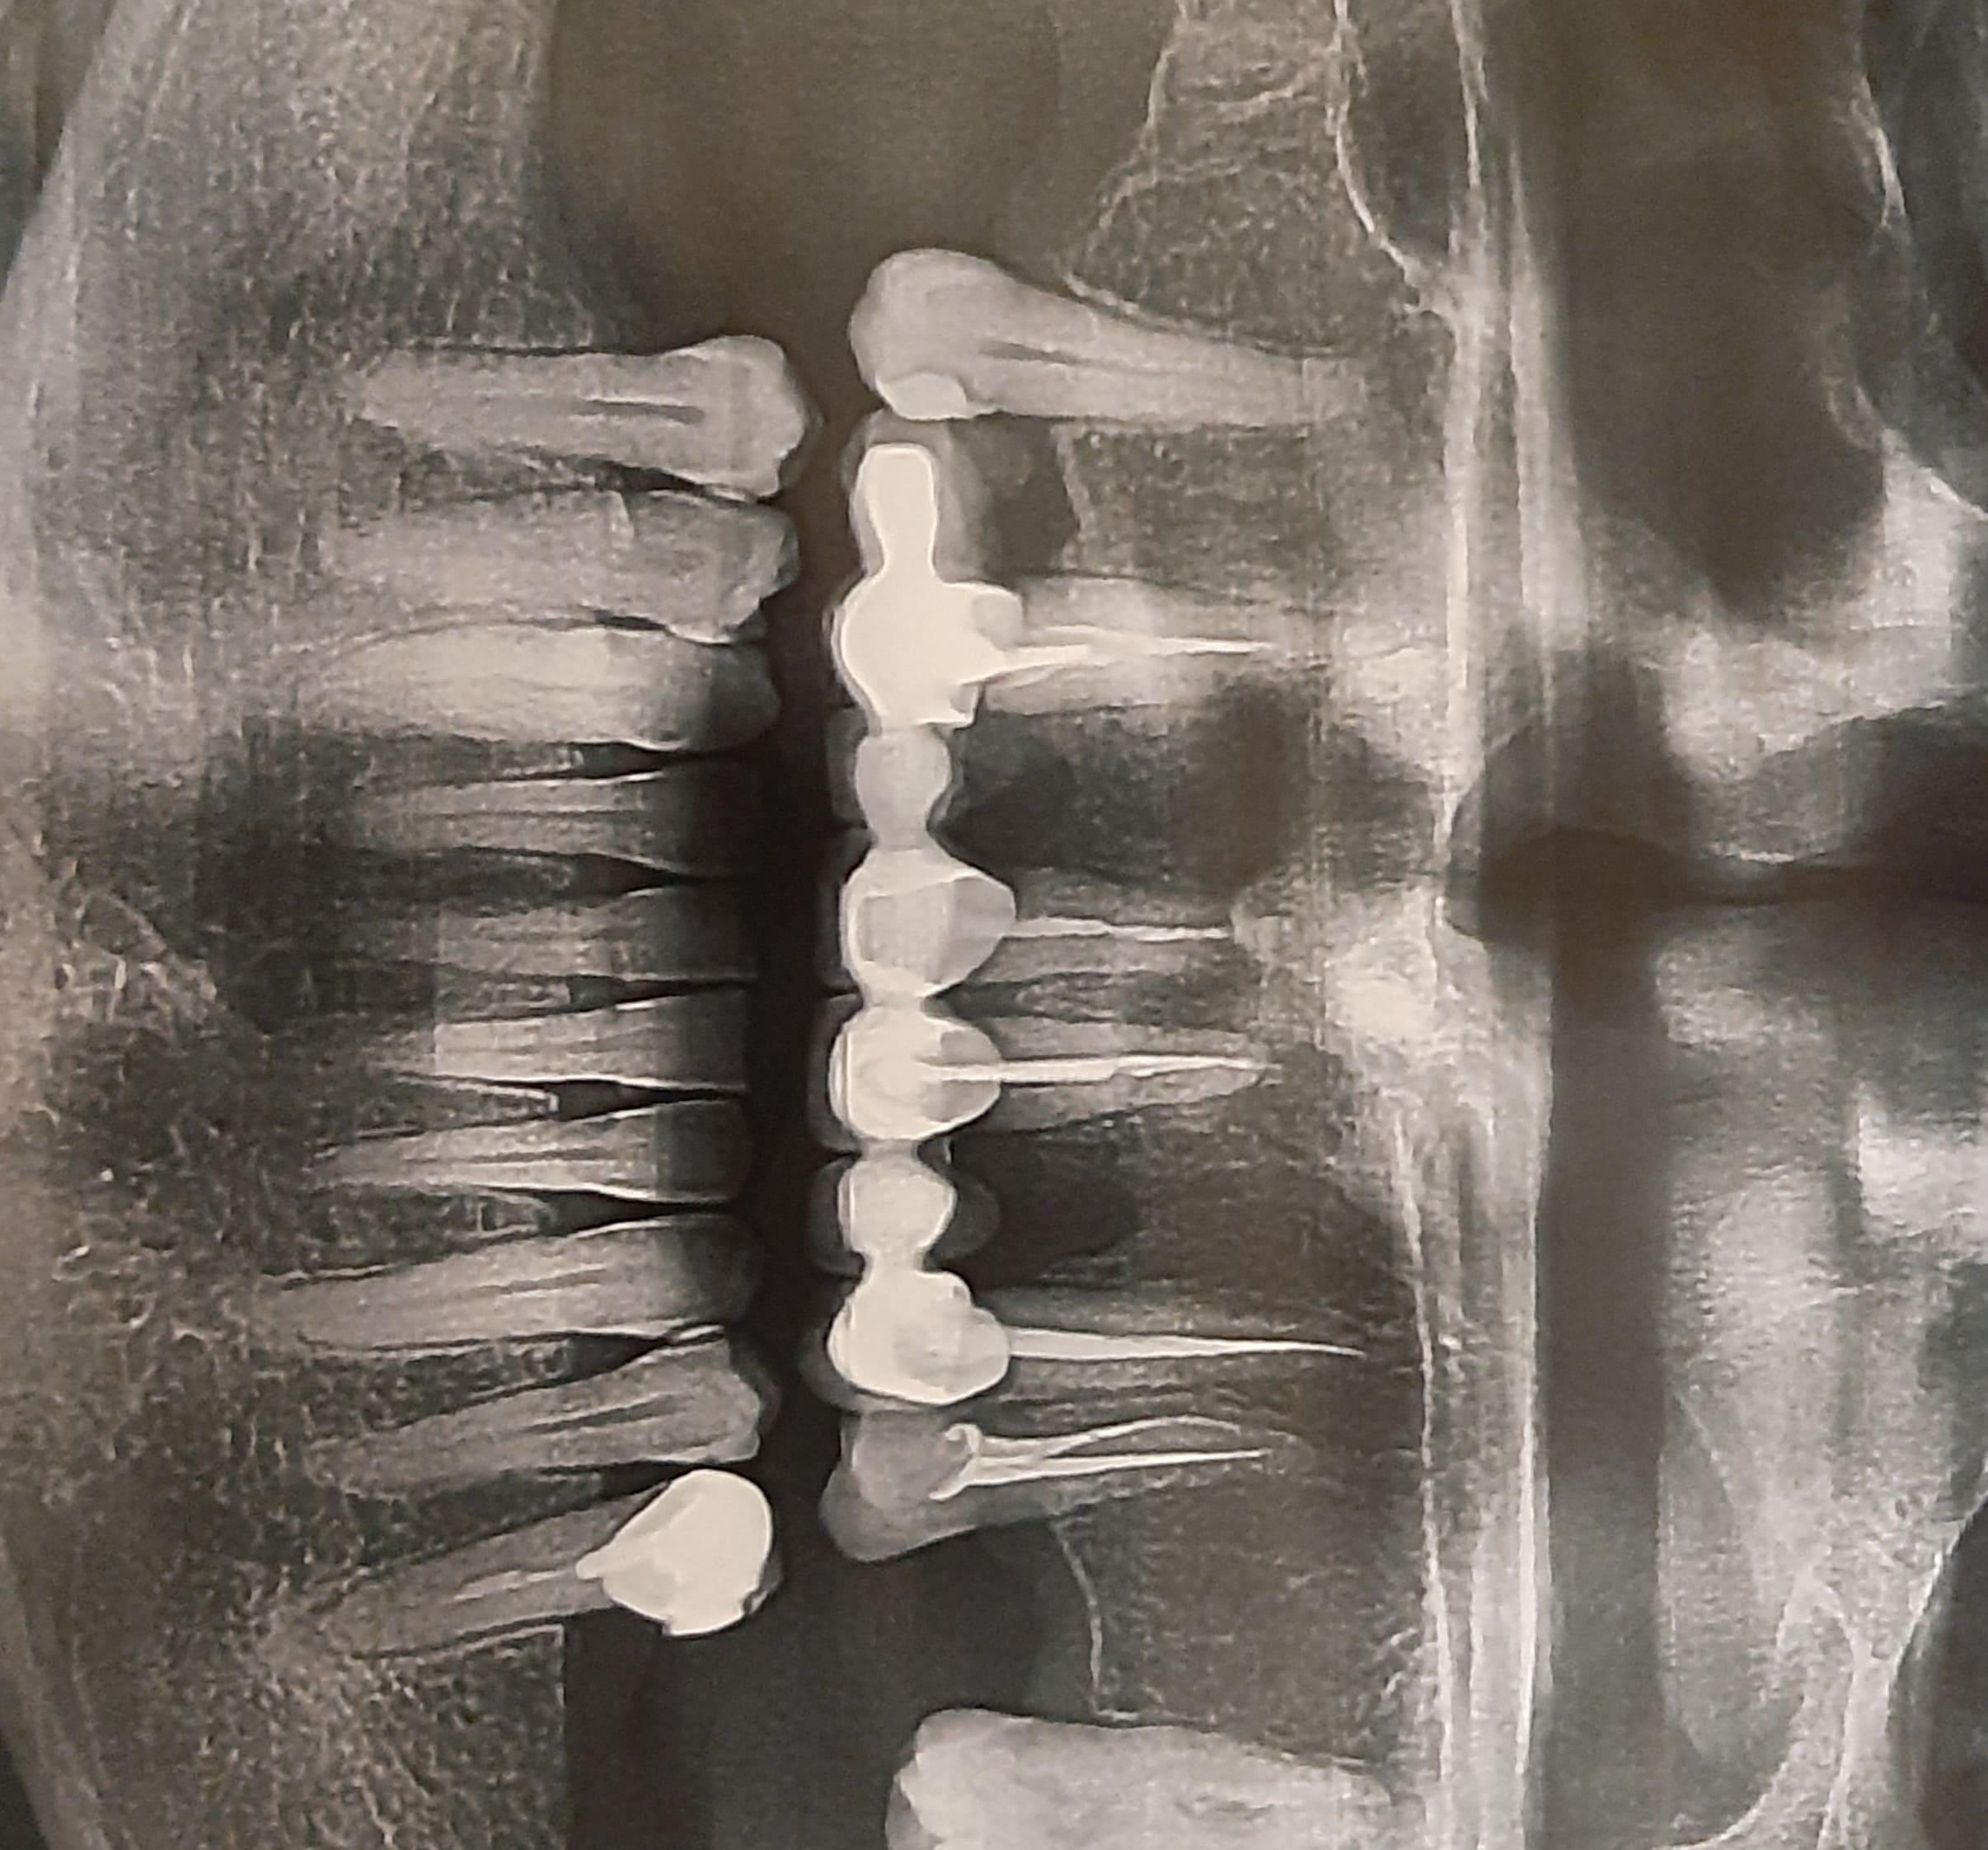

Здравствуйте, два месяца назад было воспаление корней под верхним мостом, его сняли, перелечили корни. Через месяц после перелечивания установили мост. Сегодня снова болит, по панораме мой врач ничего не увидел. Посмотрите пожалуйста свежим взглядом.